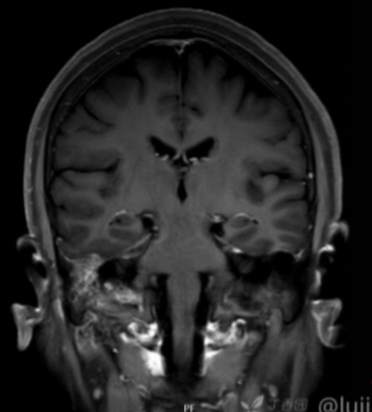

(2023-05-15 10:00,本院)行磁共振(颅脑)检查提示:右侧乳突区异常信号,考虑恶性、软骨来源肿瘤,软骨肉瘤可能性大。(集体讨论意见);脑内散在多发缺血灶。

(2023-05-12 10:15,本院)行CT(颅脑)检查提示:右侧颞骨广泛骨质破坏,伴巨大软组织肿块,性质待定,考虑肿瘤性病变,颈静脉球瘤?软骨源性肿瘤?请结合临床及病理进一步明确。